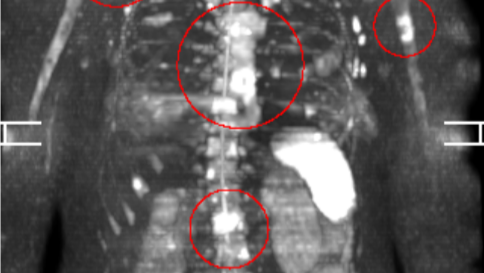

After being assured by Fred Hutchinson all was well following a lumpectomy in 2023, her naturopath was more vigilant and continued to monitor her closely. When her bloodwork began to show concerning findings, he ordered a full-body MRI scan in November 2025 (pictured above). The metastatic lesions had already spread through the pelvis, the entire spine, and the base of the long bones of her legs and arms. The image above devastated us. We called the boys up into our room and all wrapped ourselves around each other and Alicia. She has now lost 45 pounds, her body and her spirit are worn down to the bones. We must act now.

There is no cure or remission from this disease. For some with her diagnosis, the lesions quickly spread through the organs and all hope is lost. For the lucky ones with the correct supportive interventions, a longer, relatively high quality of life is achievable. Alicia has a concerning spot in her liver confirmed on her last PET scan. It was not biopsied. We are treating and hoping for the best at her upcoming follow-up scan.